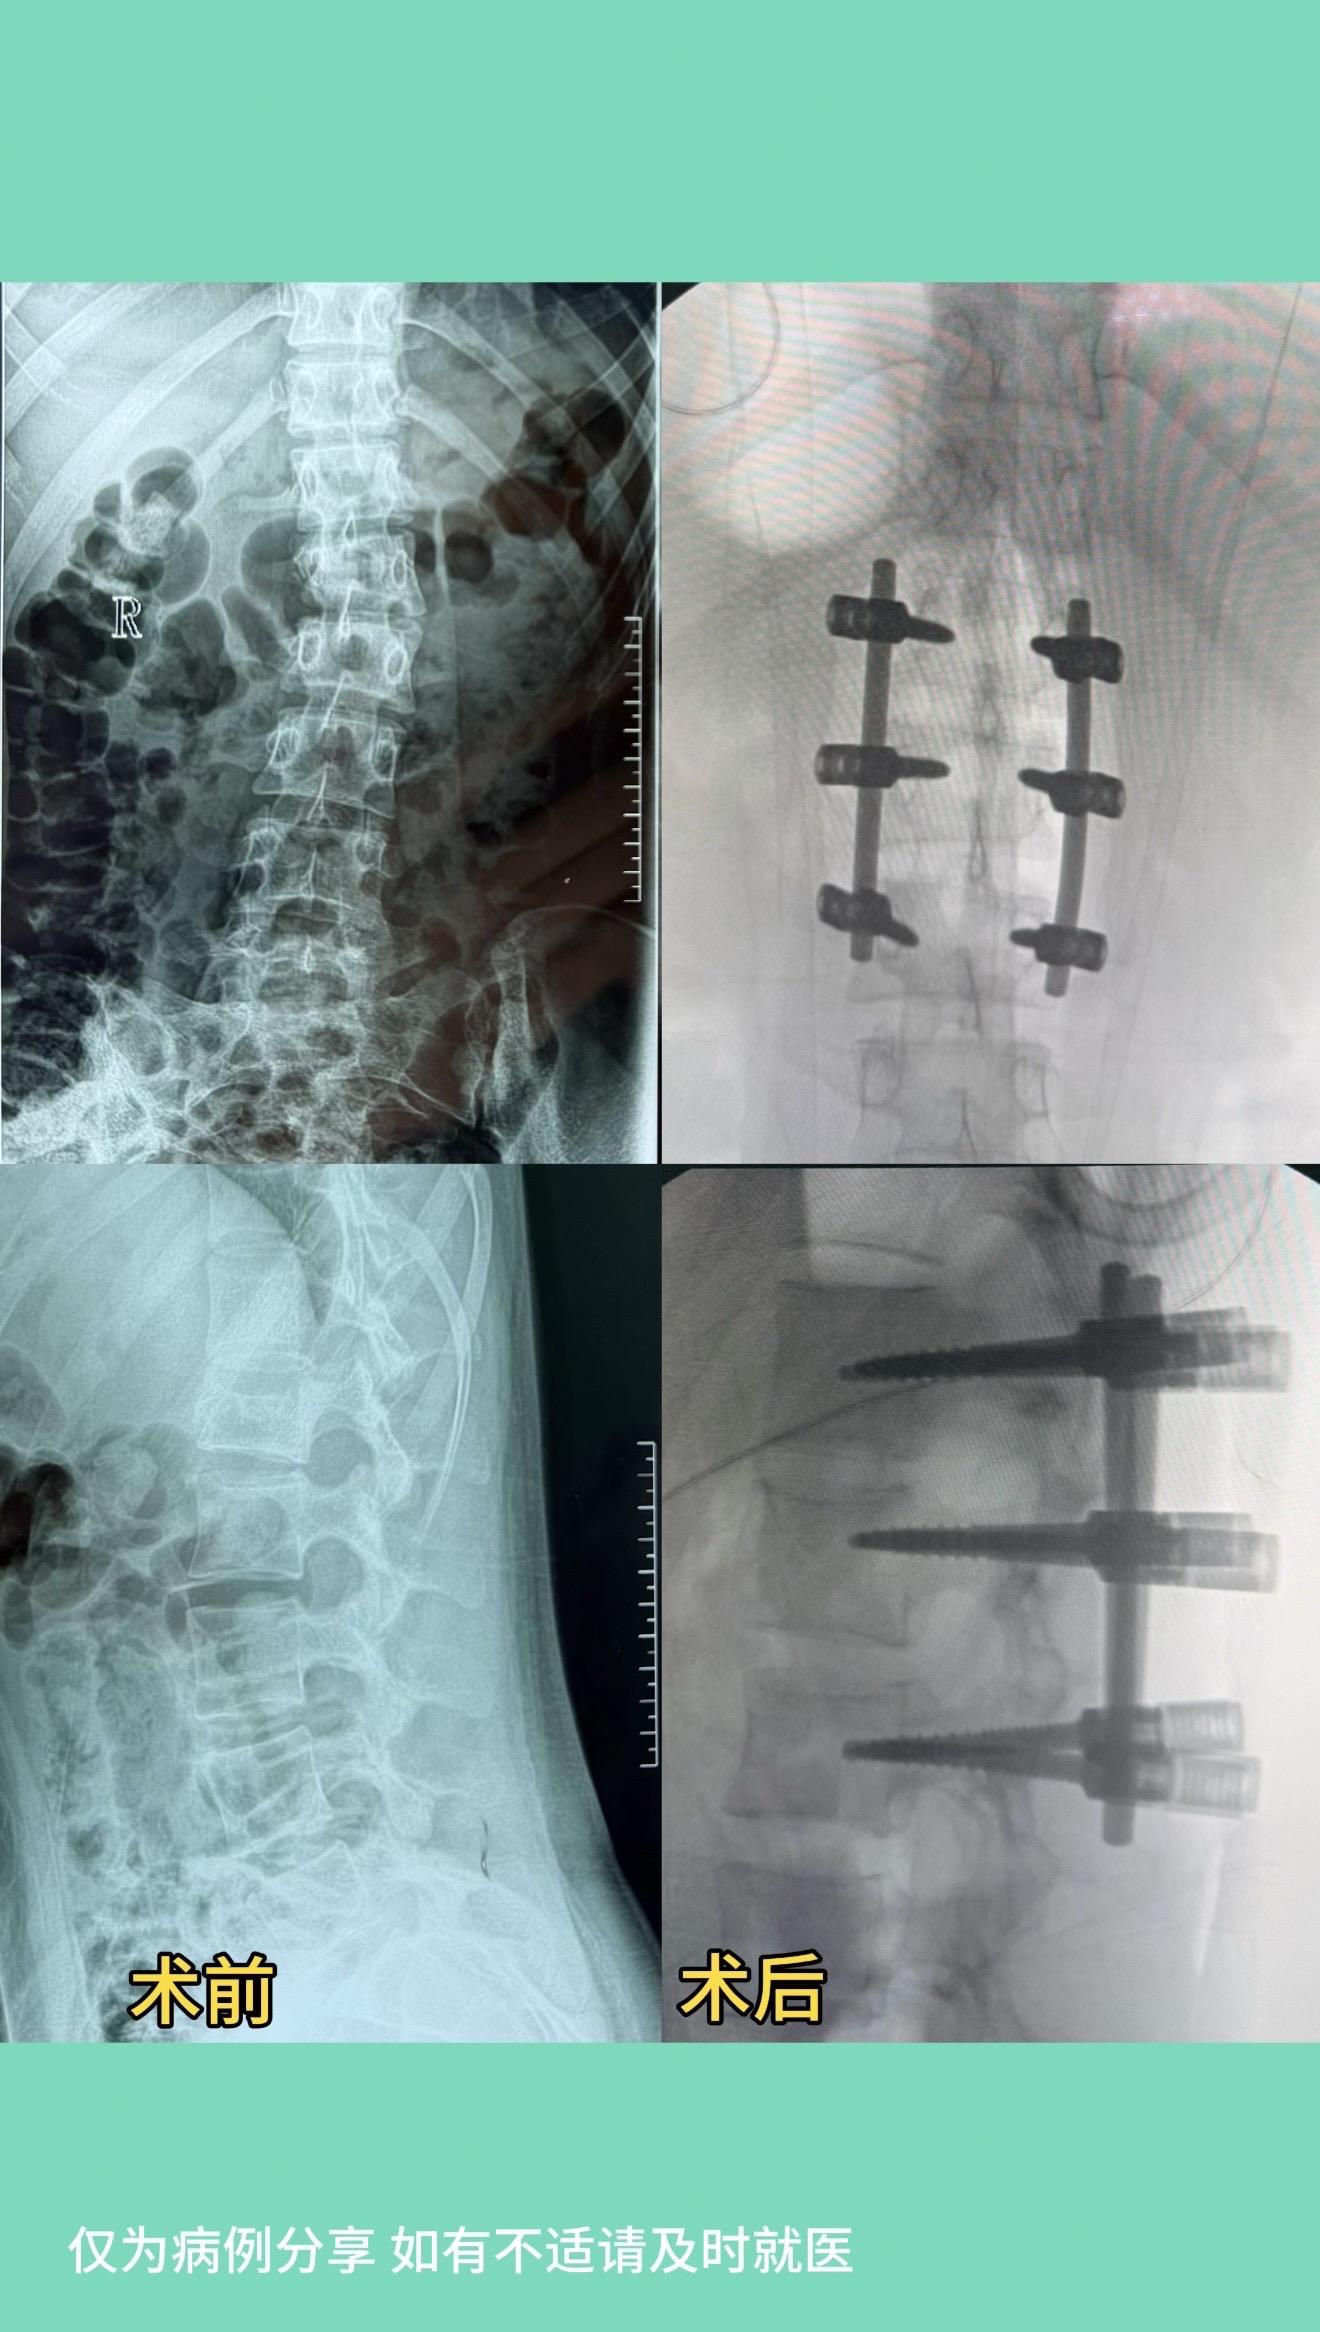

17岁女孩,车祸后腰1骨折伴侧弯,旋转畸形。术后畸形恢复好。